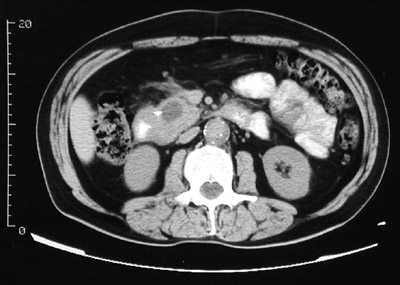

| This abdominal CT scan with contrast reveals a pancreatic pseudocyst, with a low attenuation liquefied center, in the head of the pancreas (at a lower level on CT than the pancreatic body or tail). This is not as common a location for a pseudocyst as the the tail or body of the pancreas. |